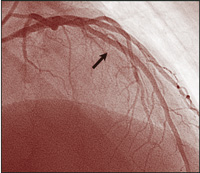

Though there have been similar case reports,17,18 ours is a unique example of an angiographically proven very late stent thrombosis, 3 years after placement of DES. During angiography 9 days prior to the event, no abnormality was noted within the previously implanted DES, nor at the stent edges before the cessation of clopidogrel therapy. Nine days after stopping therapy with this drug, filling defects were seen (Figure, B).